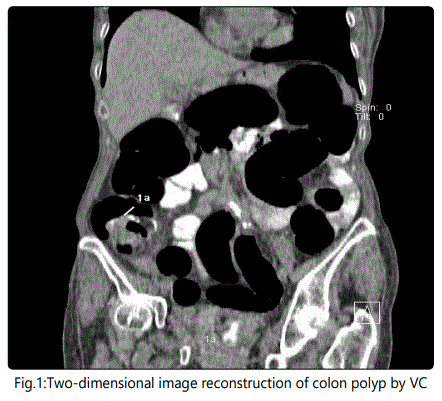

Preliminry patient's preparation consisted in three enemas and oral laxative administration. A routine OC protocol was made use of. VC protocol included the following: 12 hours prior to the imaging test, 20 mL of contrast matter was given p.o.; 4 hours before the test the patient drank iodine contrast (Ultravist®, Bayer) dissolved in 2 L of water. At VC initiation, gas was insufflated through the anus. First scanning was on abdominal position and the second one on the back with i.v. injection of contrast (3 flow 100 mL 60 sec later on). VC was performed with a 128 slash Dual Energy Siemens SOMATOM scanner. The PC software made two- and three-diomensional image reconstructions of the pathological sections (Fig. 1 and Fig. 2). Every examined study participant filled-in a questionnaire to assess his impressions with both methods - of VC and OC.